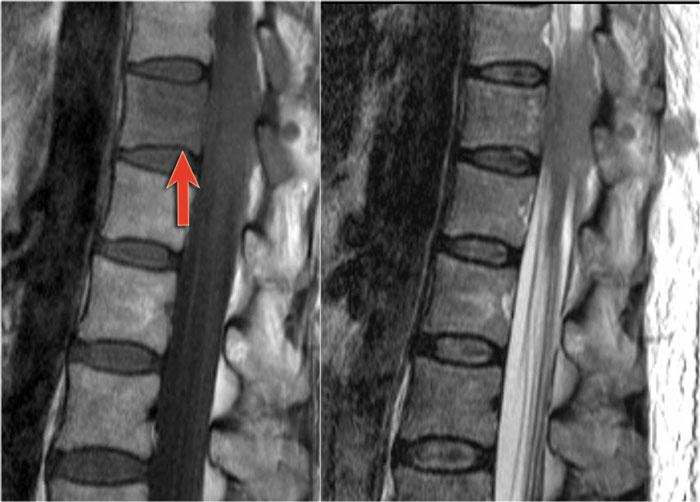

Bên trái là hình ảnh của bệnh nhân nam 60 tuổi mắc u tế bào hình sao.

Bệnh nhân nhập viện với đau vùng ngực và rối loạn cảm giác chi dưới trái, tiếp theo là liệt nửa người trái.

Có tăng tín hiệu đa đoạn trên chuỗi xung T2W kèm phù nề nhẹ, tương tự như hình ảnh đã thấy trong các trường hợp TM.

Trên CE-T1W có vùng ngấm thuốc tương phản từ.

Vùng ngấm thuốc có hình thái nghiêng về u hơn, nhưng việc phân biệt vẫn còn khó khăn.

Hình bên trái là u tế bào hình sao ở bệnh nhân 66 tuổi, nhập viện vì các triệu chứng cảm giác tiến triển dần.

Sinh thiết xác nhận chẩn đoán u tế bào hình sao.

Tiếp tục theo dõi hình ảnh tái khám.

Bệnh nhân không có chỉ định phẫu thuật và hình ảnh tái khám cho thấy bệnh tiến triển.

Lưu ý vùng tăng tín hiệu ở đoạn tủy ngực dưới và các mạch máu giãn xung quanh trên chuỗi xung T2W.

Trên chuỗi xung T1W có tiêm thuốc tương phản từ, có hiện tượng ngấm thuốc nhẹ.

Một trường hợp khác với bệnh tủy sống và giãn tĩnh mạch là hậu quả của rò động tĩnh mạch (AVF).

Một bệnh nhân khác với bệnh tủy sống và các mạch máu giãn bao quanh tủy.

Lưu ý các vùng giảm tín hiệu trên chuỗi xung T2W, biểu hiện của xuất huyết.

Một trường hợp rò động tĩnh mạch (AVF) khác với bệnh tủy sống và giãn mạch máu.

Nguyên nhân phổ biến nhất gây chèn ép tủy là bệnh lý di căn.

Lưu ý tín hiệu bất thường tại thân đốt sống do tổn thương di căn xâm lấn vào ống sống.